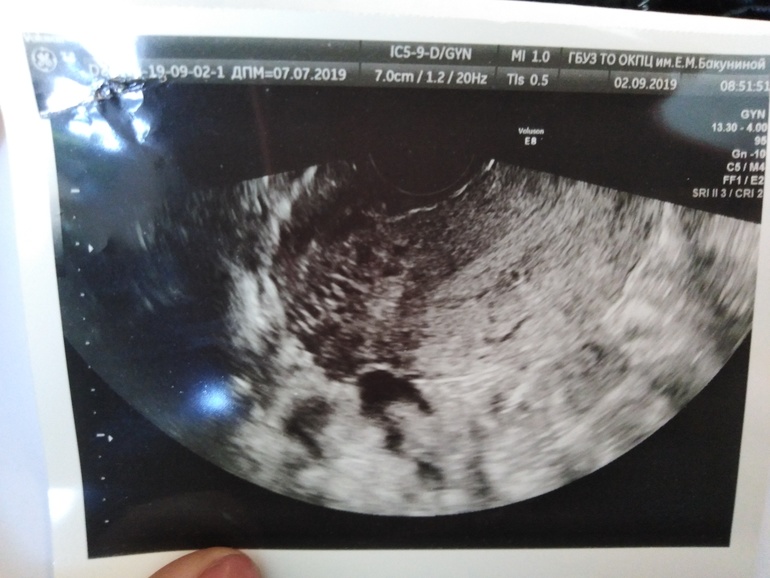

Непонятное эхогенное включение..

Задержка 29 дней, попала к врачу она отправила на узи, тесты молчат. На узи вот... Эхогенное включение нашли только тогда когда я сказала о том что болит грудь и тошнит.

Анэхогенное включение 3,4 мм - это конечно не 7 дпо точно, если это эмбрион, по идее это размер почти 5 недель беременности, но тогда и тест должен быть яркий. А если это 7 дпо, то тогда это не эмбрион( В общем, я бы на жидкость не равнялась.

тот кружочек который справа его и нашла врач в последний момент.